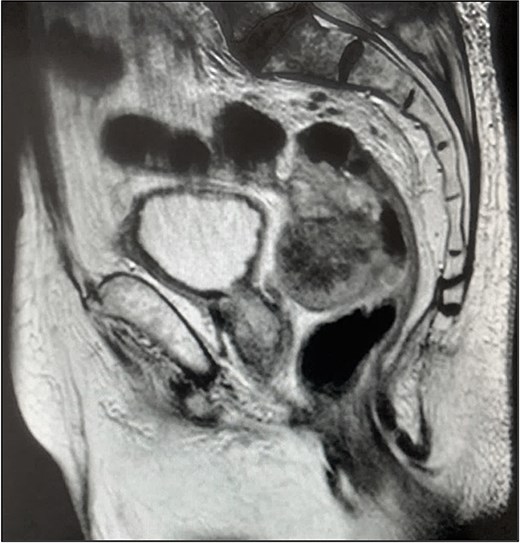

Pelvic magnetic resonance imaging (MRI) revealed a extrarectal lesion located 8 cm from the anal verge, with 4 × 4 cm, suspicious of tumoral deposit in the mesorectum (Figs 5 and 6).

The patient underwent an exploratory laparotomy with segmental enterectomy of approximately 30 cm of jejunum (Fig. 7) and Hartmann’s procedure with partial mesorectal excision. The postoperative course was complicated with a pelvic abscess, managed with CT guided percutaneous drainage and antibiotic therapy. The patient was discharged on the 23rd postoperative day.